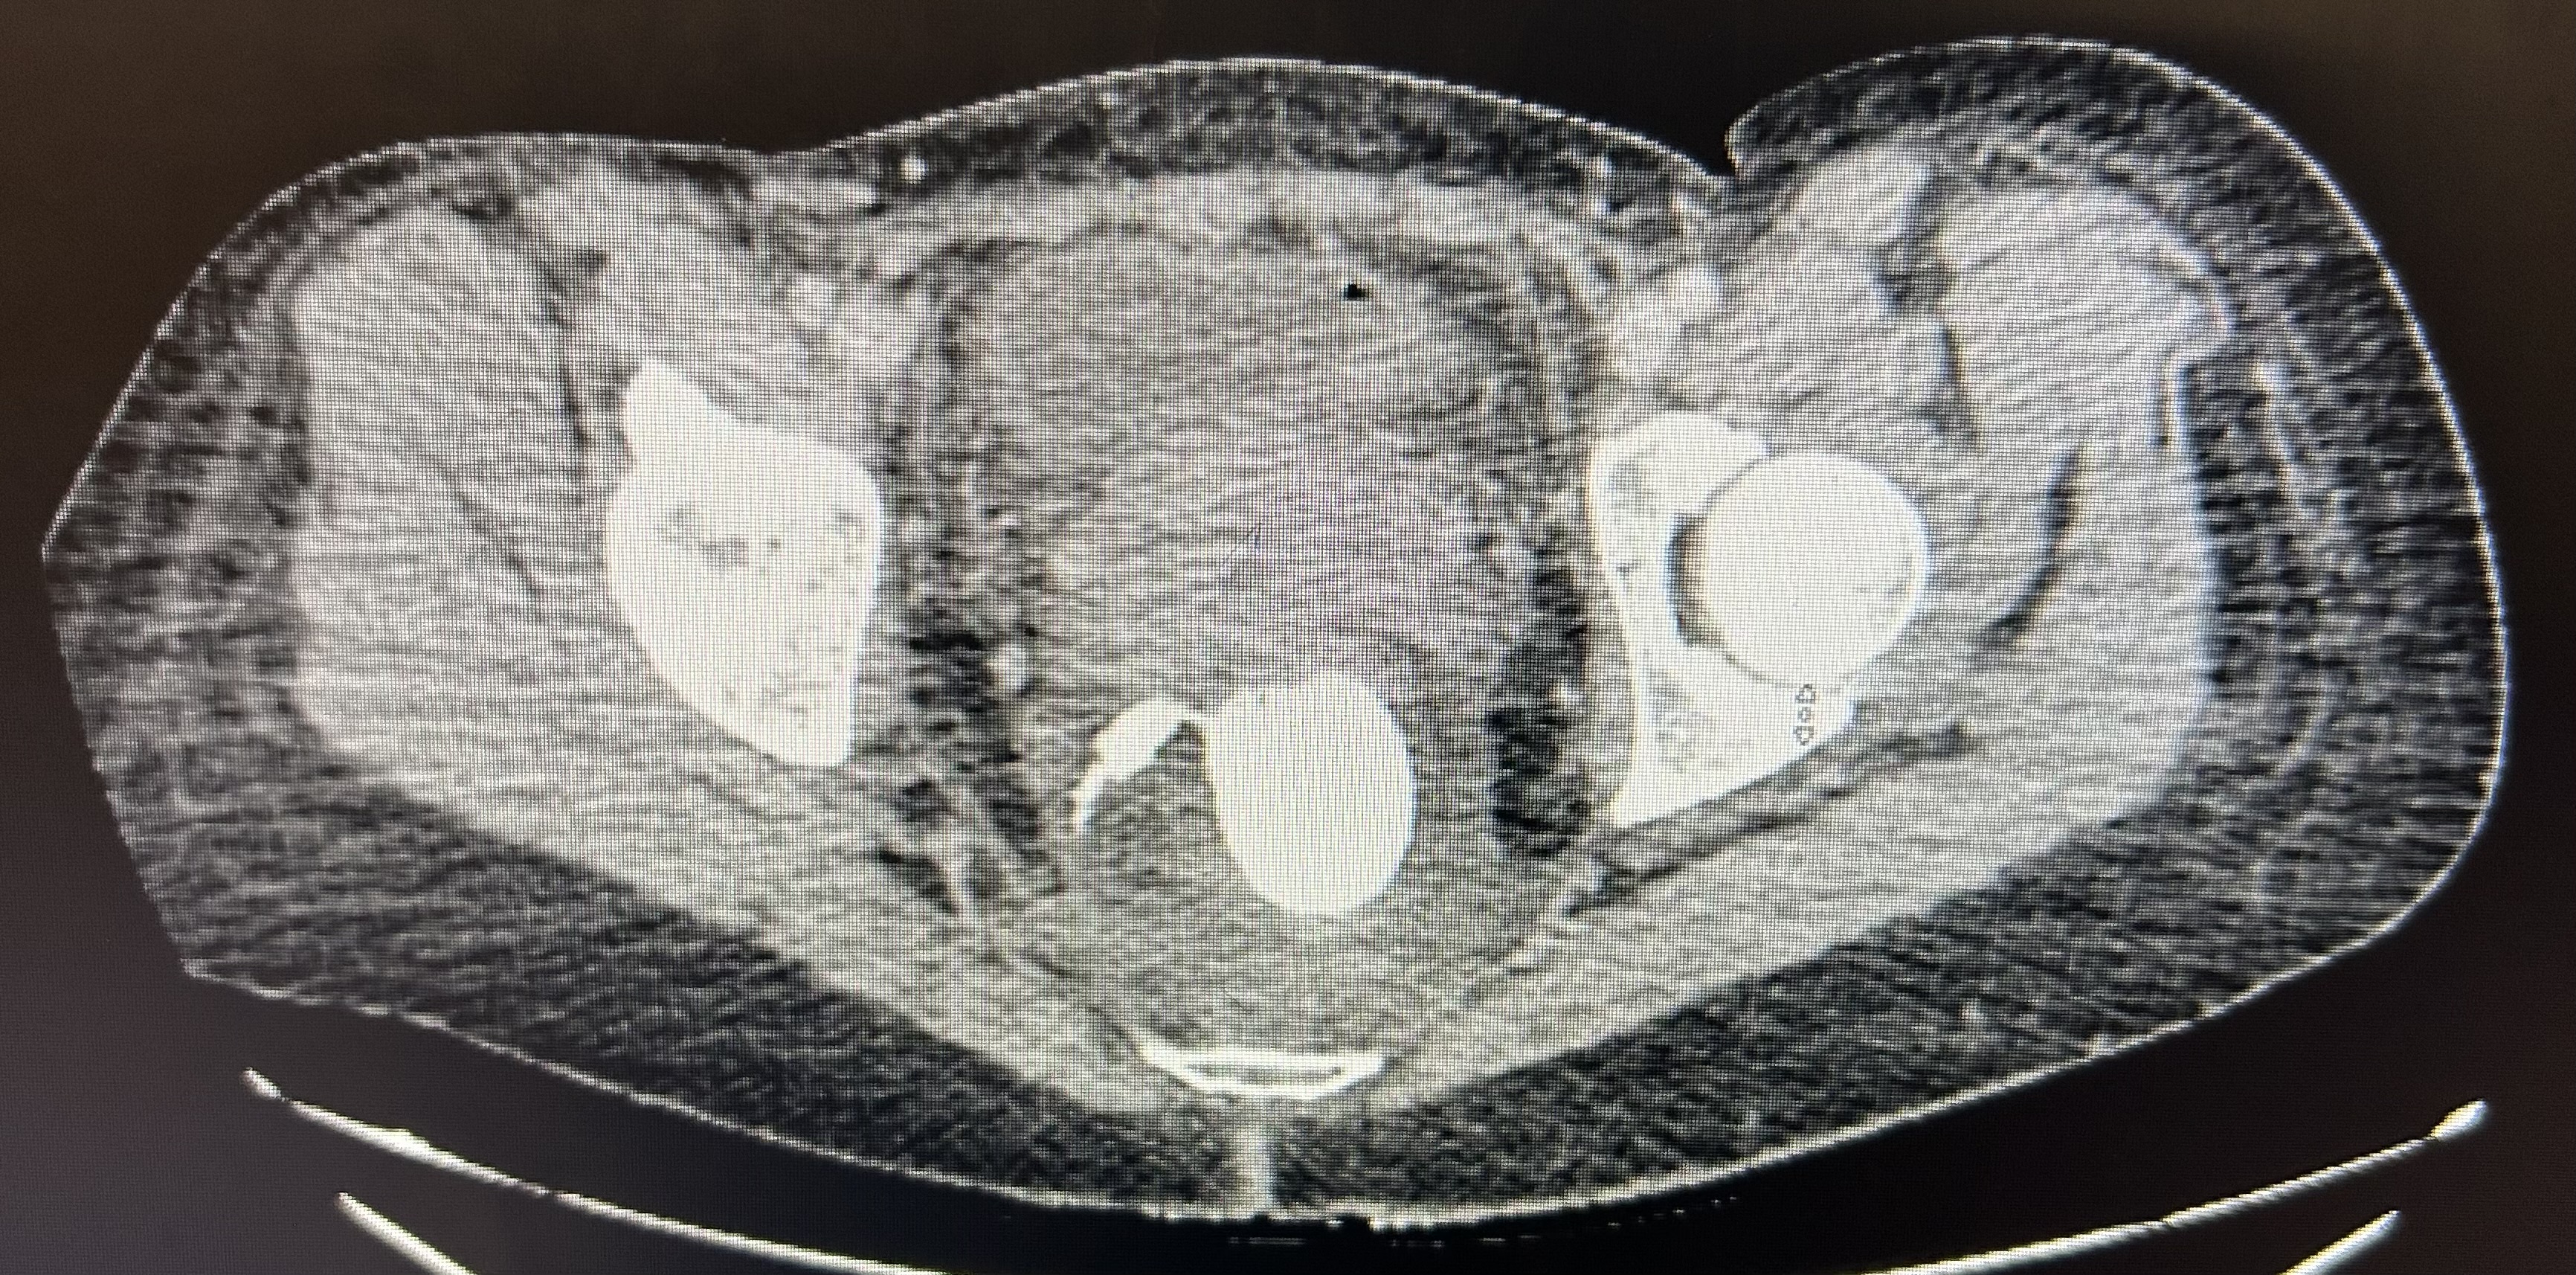

Initial CT imaging notable for air within the mesorectum and peri-rectal soft tissue edema